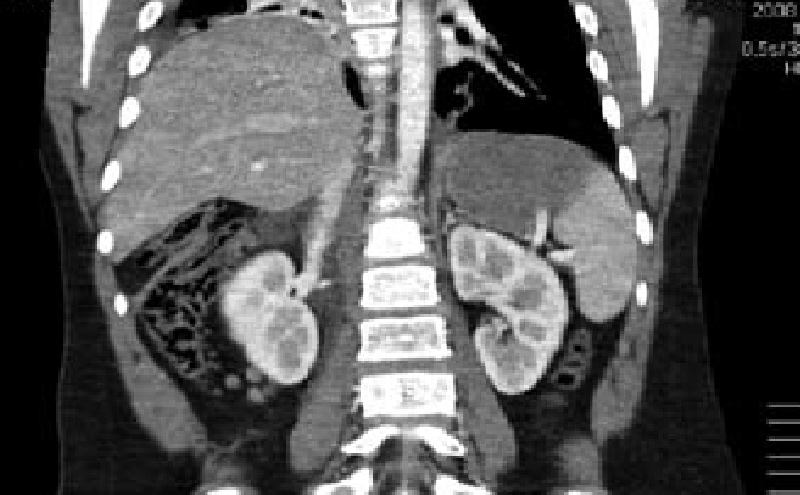

A 19 year old previously healthy male, NCAA defensive end, presents with four months of intermittent, non-exertional, midsternal chest pain and pressure. The pain is described as an episodic band like pressure radiating across the epigastrium. At maximum the pain is rated four out of ten and is completely relieved with holding a deep inspiration. There are no other mitigating or exacerbating factors. There are no other associated symptoms. This has never happened previously. Initial workup in the emergency department with chest radiograph revealed a right cardiophrenic angle mass. Electrocardiogram, complete blood count, comprehensive metabolic panel, lipase and troponin were within normal limits. Computed tomography scan revealed intrathoracic herniation of the left lobe of the liver through a large Foramen of Morgagni hernia over the right aspect of the heart. The patient obtained cardiothoracic surgery consultation and opted to forego surgical intervention while symptoms remained mild to moderate. The patient successfully returned to play and completed a full season as an NCAA defensive end without complication. The patient has another year of eligibility and plans to complete his collegiate career without surgery if symptoms remain stable.